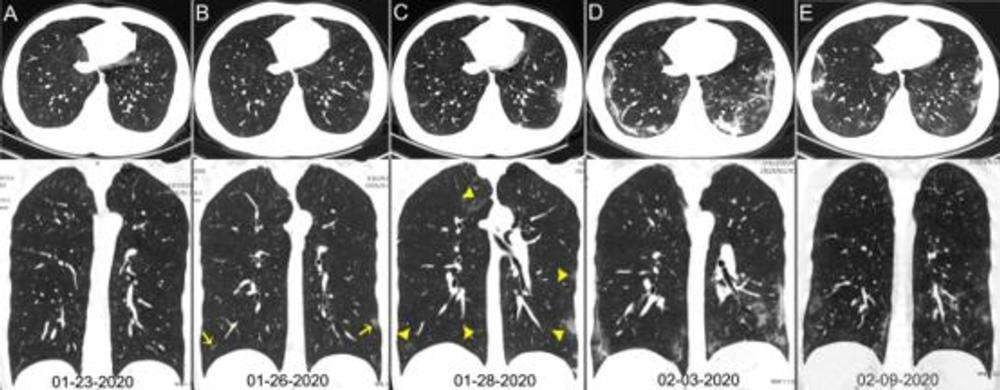

COVID-19'un akciğerlere olan etkisi spesifik olduğundan doktorlar, sadece CT taramalarına bakarak hastalığı çoğu zaman teşhis edebiliyorlar. Enfeksiyonun açık belirtilerinden bazıları, akciğerlerdeki hava boşluklarının sıvı ile dolması, oksijen ve karbon dioksit moleküllerini değiştiren küçük hava keselerinin çökmesi. Bunu CT taramalarında, yukarıdaki resimdeki sarı oklarda görebilirsiniz.